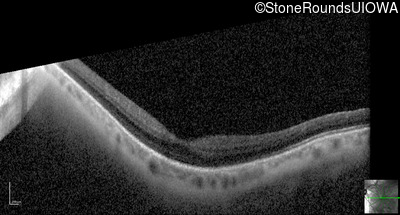

Optical Coherence Tomography - Left - 20/25 +2

Exemplar / OCT Stack